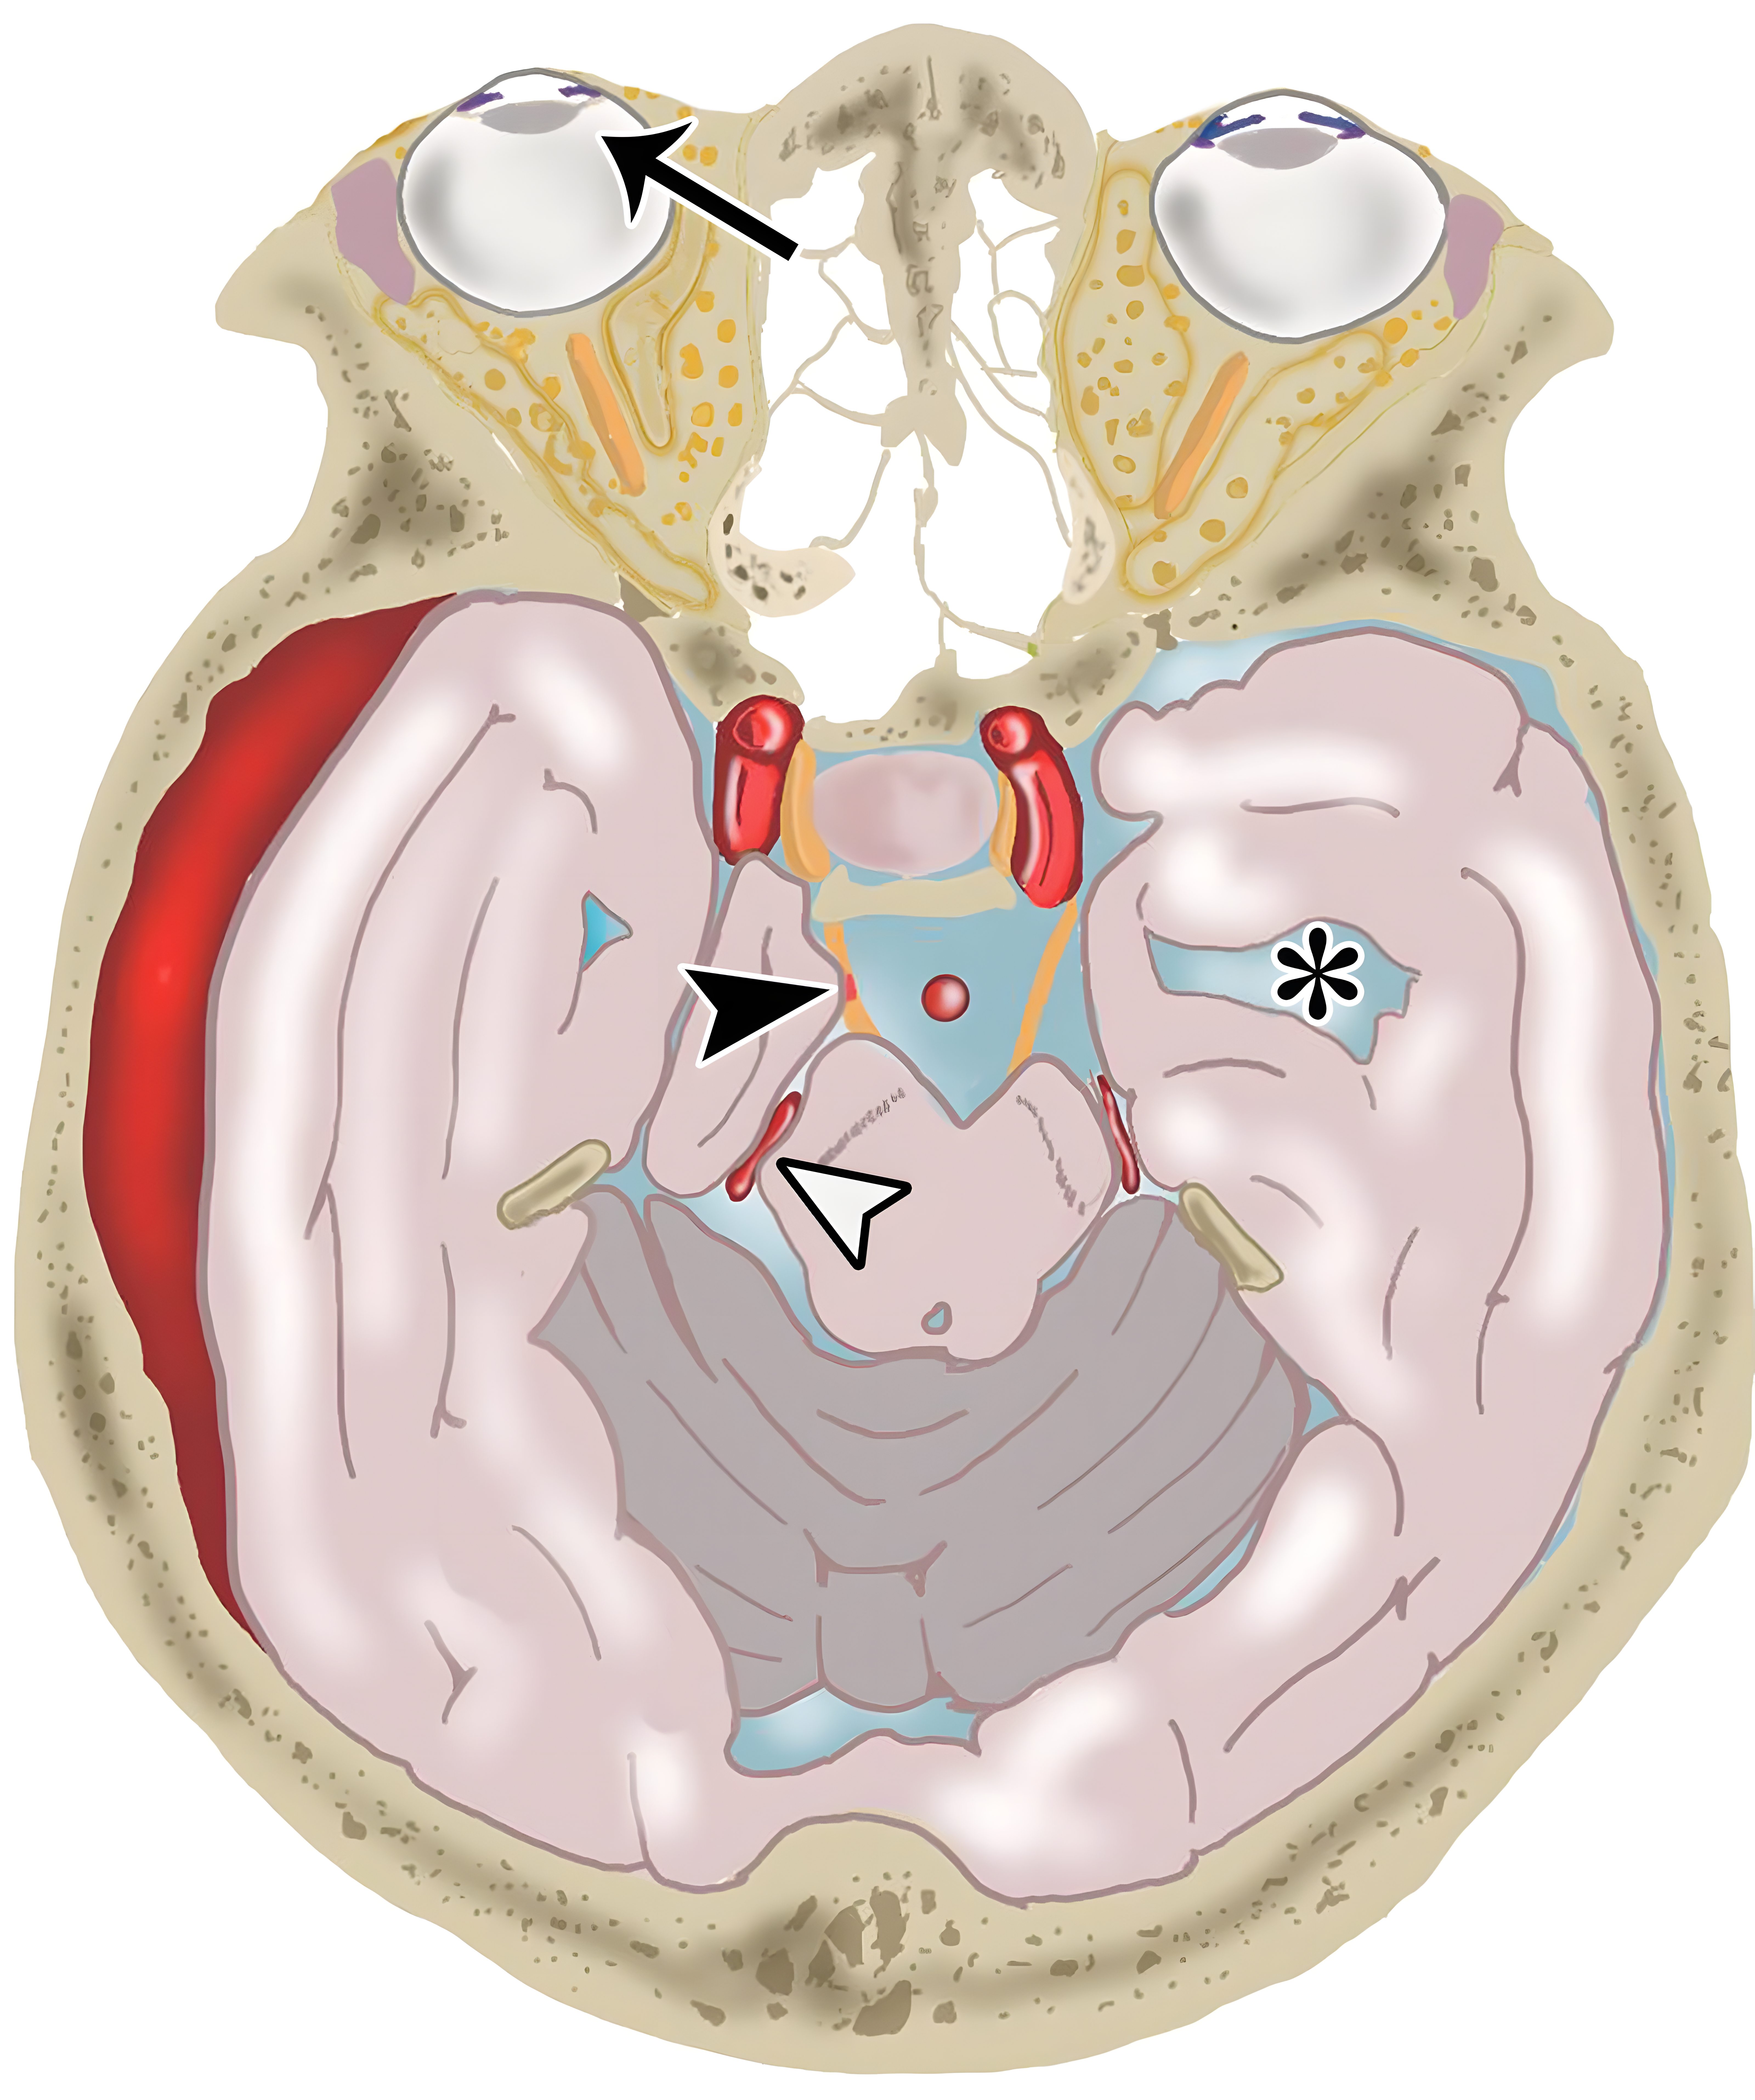

338eacde522c534fcbe30a562cfb64f4.jpeg

中脑导水管(白色短箭头),大脑后动脉(白色长箭头),大脑脚池(CrC),海马回(HG),大脑脚间池(IPC),中脑周围池(PMC),四叠体池(QC),钩回(U)。